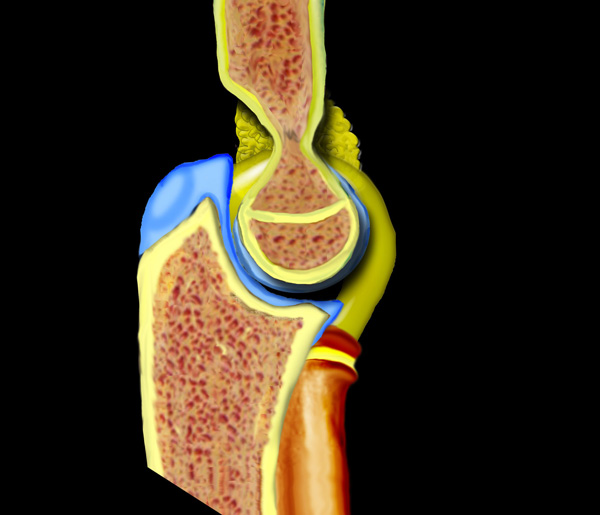

Chấn thương khớp khuỷu tay thường là kết quả của tình trạng duỗi quá mức hoặc vẹo ngoài quá mức do ngã chống tay ra phía trước.

Cuộn qua các hình ảnh ở bên trái để xem cách duỗi quá mức dẫn đến gãy xương trên lồi cầu.

Tình trạng tràn máu khớp sẽ dẫn đến sự dịch chuyển của đệm mỡ phía trước lên trên và đệm mỡ phía sau ra phía sau.